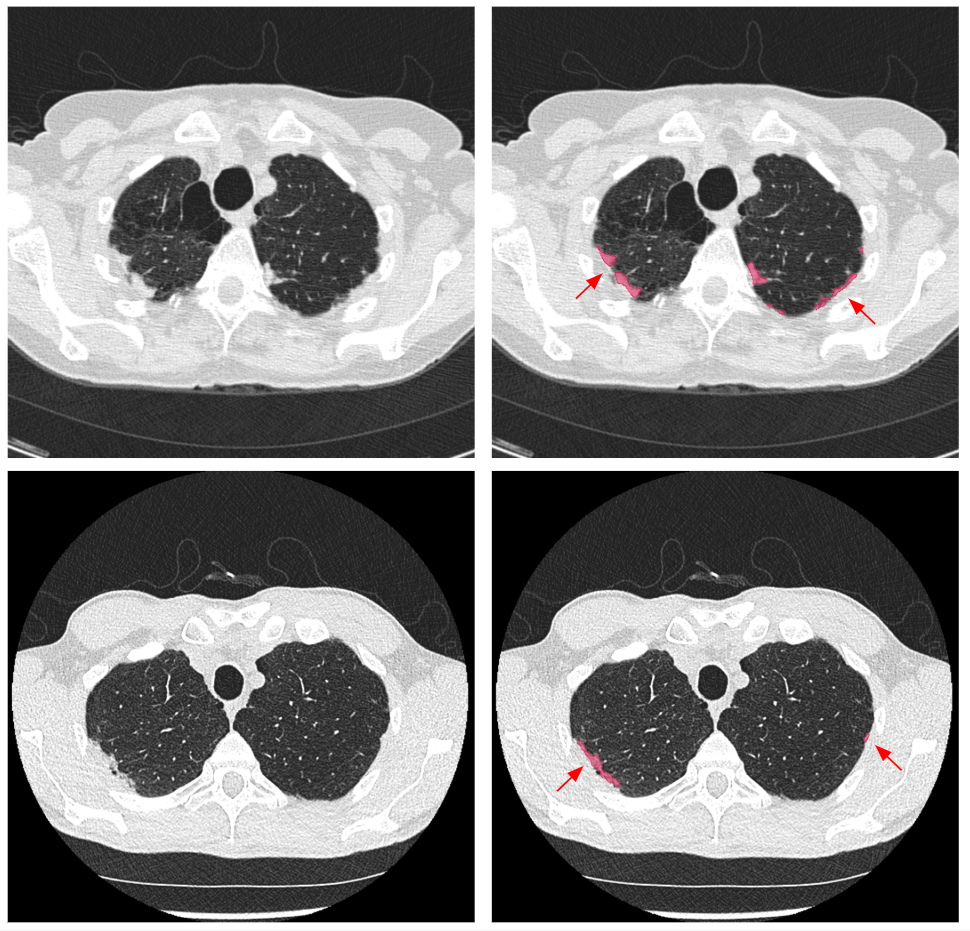

Refer to caption

Figure 3: Representative examples of automated PPFE quantification on axial CT images from the NLST and SUMMIT cohorts. The first column shows the original CT images, and the second column shows the corresponding CT images with automated PPFE segmentation overlaid. Highlighted regions (red) indicate PPFE identified by the automated segmentation model in the upper lung zones. The first row shows images from a 65-year-old female participant in the NLST cohort with a quantified PPFE volume of 8.85 cm3. The second row shows images from a 55-year-old male participant in the SUMMIT cohort with a quantified PPFE volume of 5.32 cm3.

For each participant, PPFE lesions were automatically segmented on baseline and follow-up low-dose CT scans. PPFE volume was quantified by multiplying the number of voxels classified as PPFE by the voxel dimensions, yielding a total volume in cubic centimetres (cm3) for each scan. These quantitative PPFE measures were subsequently used to derive longitudinal PPFE change metrics for downstream statistical analyses. An example of automated PPFE segmentation is shown in Figure 3.